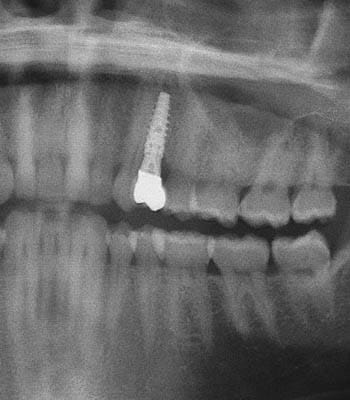

Dental implants are a titanium "root" which can be placed into the jawbone. Once integrated with your bone, the implant can be used to support a crown, a bridge, or secure a complete denture. Dental implants may be used to eliminate partial plates and dentures. The success rates for dental implants are extremely high which is due in part to the fact that root-form implants are made of a biocompatible material, titanium.

Single Tooth Replacement